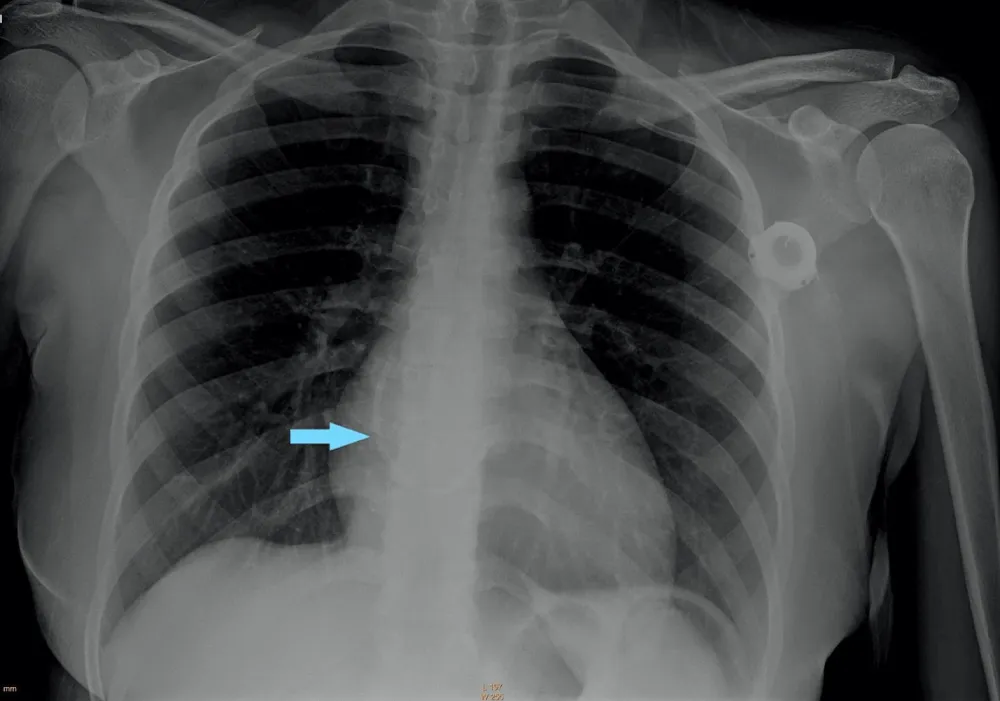

A 24-year-old woman with immune thrombocytopenia managed with intravenous immunoglobulin infusions through a chest port catheter was admitted to our emergency room after experiencing chest discomfort with sudden onset while receiving the infusion. She did not appear to be in any acute distress and her vital signs were stable. Electrocardiography was unremarkable. Laboratory tests showed troponin values within the normal range. Further workup with chest radiography revealed that the chest port catheter was fractured and had migrated to the right atrium (Figure 1).

Figure 1: Chest radiography shows a fractured chest port catheter in the right atrium (blue arrow).